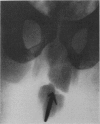

An Unusual Urethral Foreign Body *